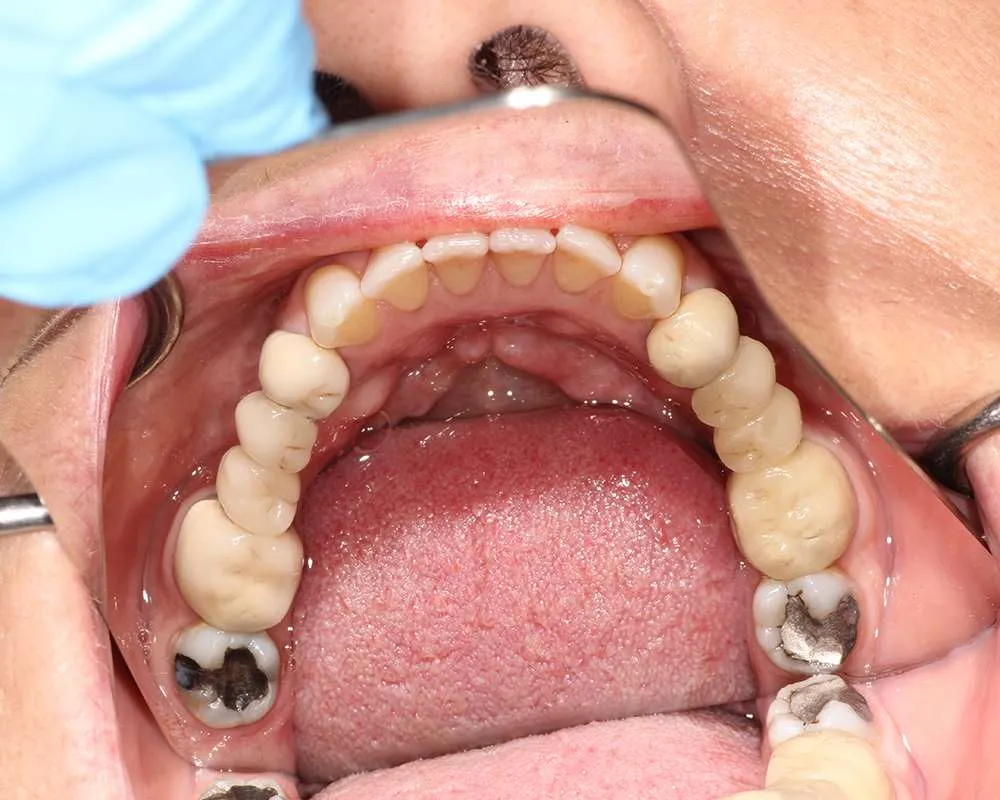

Real Stories, Real Results: Case Studies Showcasing How Our Personalized Approach Transforms Smiles and Lives

Complex Cases

Witness the Remarkable Changes We Can Achieve

The safe removal of mercury fillings is crucial for your health and well-being. At our practice, we follow strict protocols to ensure that mercury amalgam fillings are removed safely and effectively.